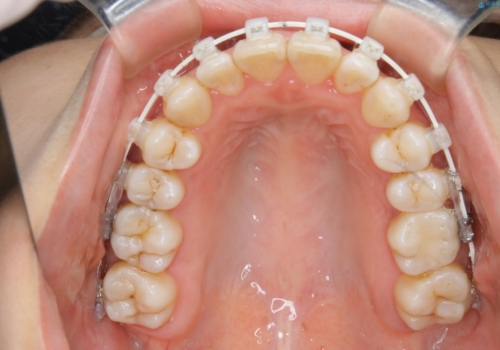

- 矯正装置

- ワイヤー矯正 審美装置

- 治療計画

- 歯のガタつき、顎のズレ、出っ歯を気にして来院された患者様です。

歯を抜きたくないとの希望であったためマウスピース治療をお勧めしましたが、

マウスピースをずっとつけていることは難しいとの事であったためワイヤー矯正治療を行うこととなりました。